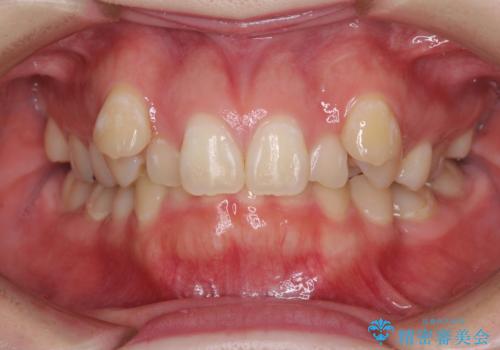

- 八重歯と下顎小臼歯の欠損を気にして来院された患者様です。

下顎小臼歯の欠損により過蓋咬合となっていたため、下顎は臼歯を起こすことで咬み合わせを改善し、八重歯は第一小臼歯2本を抜歯し、補助装置を使用して速やかに改善することとしました。

八重歯は3,4か月で速やかに改善されました。